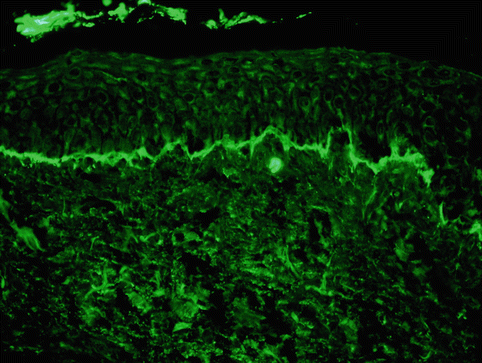

Histology as well as immunofluorescent testing is required to confirm the diagnosis. Histologic examination reveals a subepidermal blister with a predominantly neutrophilic infiltrate in the papillary dermis. Mononuclear cells and occasional eosinophils can also be seen (Fig. 34.3). Immunofluorescent testing of perilesional skin is the gold standard for diagnosis and is characterized by linear IgA staining of the BMZ (Fig. 34.4). For unclear reasons, it is recommended that one should avoid using the volar forearm as the site for biopsy, as immunofluorescent testing in this location may be falsely negative [15]. On salt split skin, autoantibodies bind to the epidermal side in most patients; however, antibody binding to the dermal side or to both the epidermal and dermal side occurs in some cases [16]. Circulating autoantibodies are of the IgA1 subclass [17] and can be found in over 90 % of patients [18]. A subset of patients manifest clinically as CBDC but show a mixed pattern of IgA and IgG antibodies on immunofluorescent testing; this entity has been termed “mixed immunobullous disease of childhood” and is similar to CBDC in terms of target antigens, disease presentation and course, and response to treatment [19].

Fig. 34.4

Direct immunofluorescence demonstrating linear deposition of IgA along the basement membrane zone (Courtesy of Dr. John Zone, University of Utah. Reprinted from Dermatology Clinics, Autoimmune Blistering Diseases: Part I – Pathogenesis and Clinical Features, 29/3, Mintz EM, Morel KD, Clinical Features, Diagnosis, and Pathogenesis of Chronic Bullous Disease of Childhood, Pages 459–462, (2011) with permission from Elsevier)